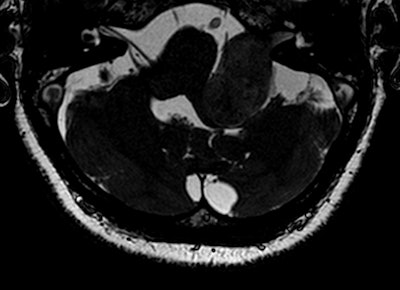

Postgadolinium T1-weighted image shows lesion (left: original image; right: lesion marked in red).Most of the controversies regarding the use of gadolinium focus on the primary diagnosis -- rather than follow-up and post-treatment -- of vestibular schwannoma, which is a benign intracranial tumor of the myelin-forming cells of the vestibulocochlear nerve in the internal auditory canal next to the brain. Patients may present with sensorineural hearing loss, tinnitus, and balance problems, but only a small percentage of people with these symptoms will have vestibular schwannoma, explained Dr. Berit Verbist, a neuro and head and neck radiologist at Leiden University Medical Centre in the Netherlands.